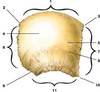

Arterial Grooves

11, 12, 13

External Table

Diplöe - spongy inner portion analogous to the trabecula in long bones

Internal Table

Superior sagittal sulcus

the groove for the superior sagittal sinus is a depression formed on the internal surface of the frontal, parietal, and occipital bones in the midline.

It courses from the frontoethmoid junction to the internal occipital protuberance.